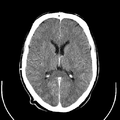

معرض الصور